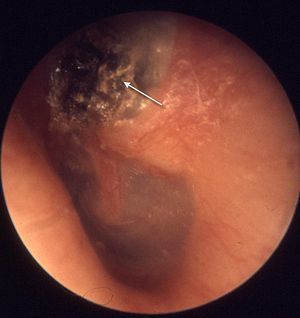

What’s seen on otoscopy in cholesteatoma?

‘attic crust’ - seen in the uppermost part of the ear drum